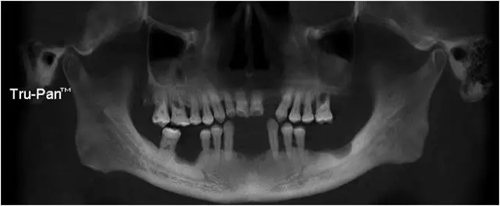

22缺失,21與23之間間隙大于12,切牙齦退縮明顯(圖1)。全景片示 22缺失處齒槽嵴高度和寬度及密度尚可(圖2)。

圖1 術(shù)前口內(nèi)照片

圖2 術(shù)前影像學檢查